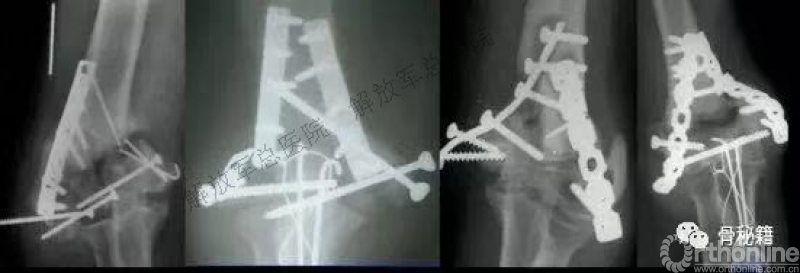

看看这些失败的case,肱骨远端不简单!

然而

AO固定技术流程,会让骨折简单起来!